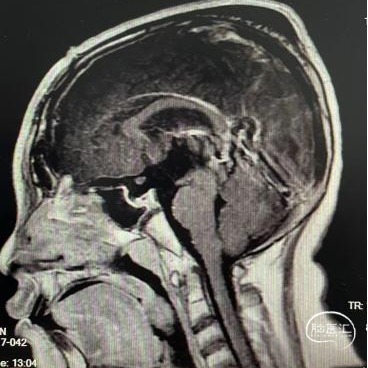

头部MRI显示:鞍区-鞍上区-第三脑室可见一不规则囊状长T1极长T2信号灶,大小约43mm*32mm*43mm,增强后可见病灶不均匀明显强化。垂体及视交叉未见显示,双侧脑室扩张,双侧脑室旁可见对称性斑片状长T1长T2信号灶。

综合该患者术前资料,考虑第一诊断为颅咽管瘤。术前曾考虑经蝶入路。但分析影像学资料后认为其囊内容物可能并非全为液态成分。遂实施开颅手术切除肿瘤。